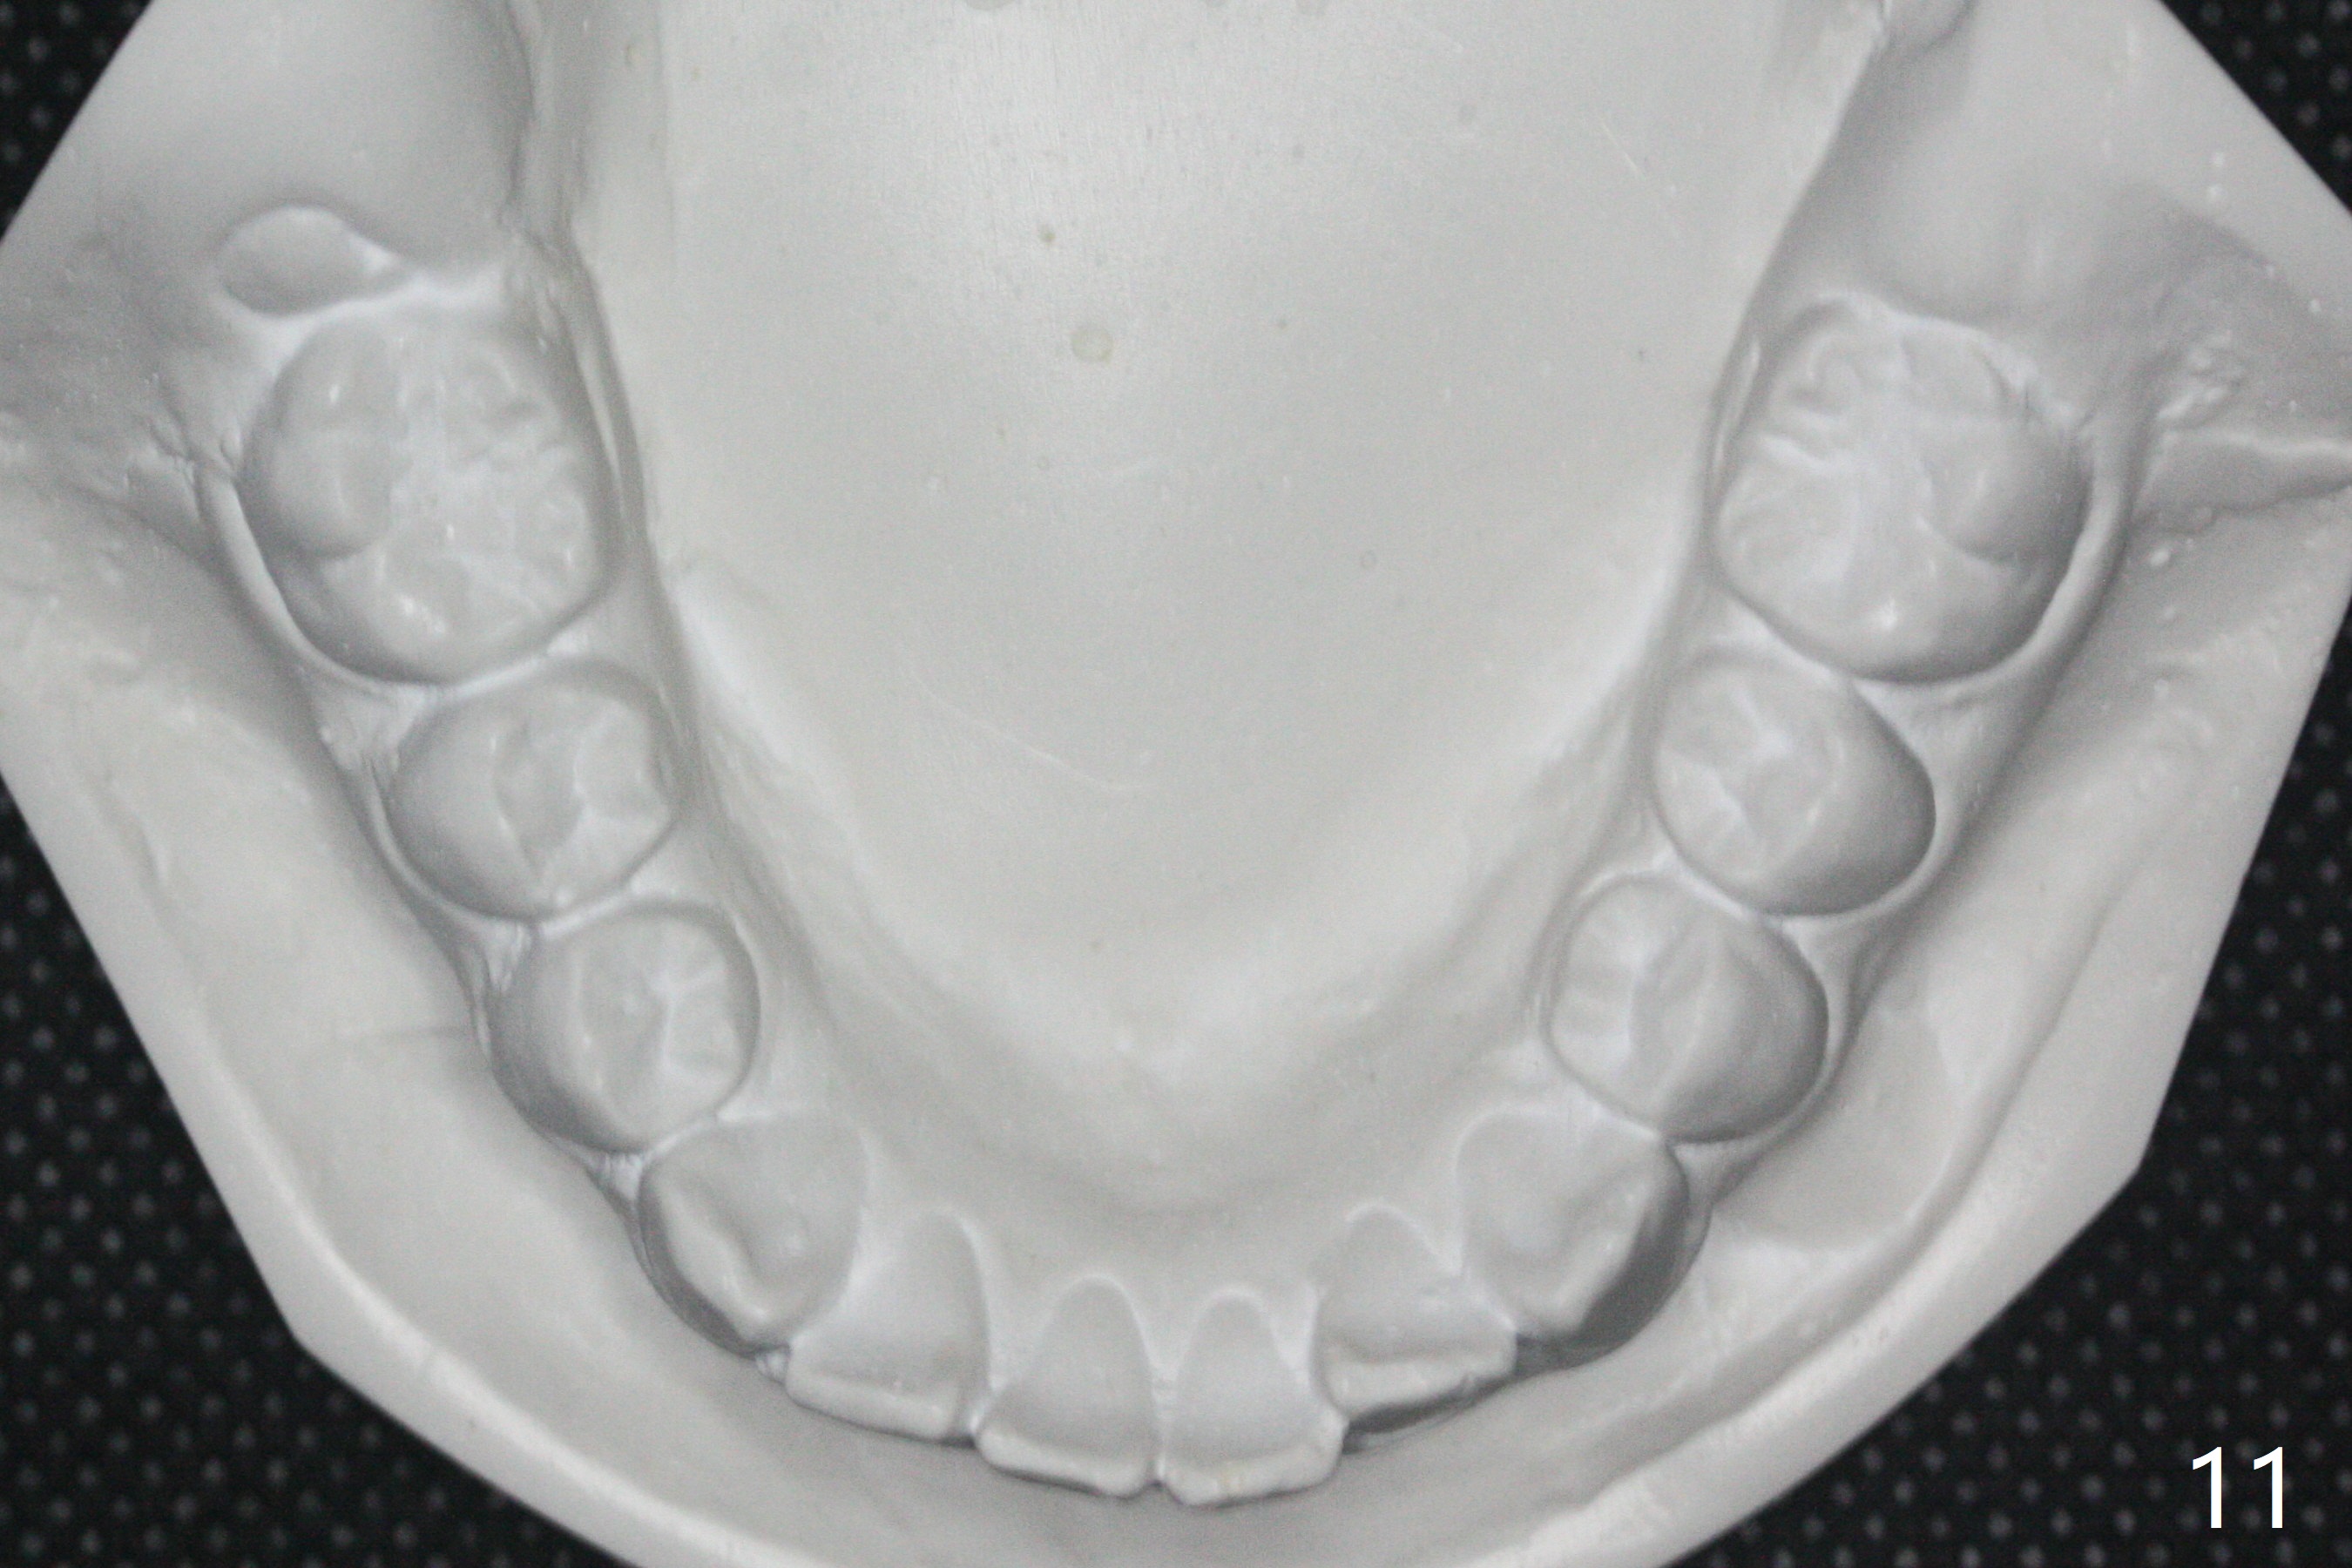

Facial Class I Occlusal Class II

A 12-year-old woman has Class I facial profile (Fig.1-4,12,13) and apparently Class II Division I malocclusion (Fig.6-11). Start Class II retraction as early as possible to take advantage of the upper and lower posterior diastemata (Fig.9,11 (in fact there is no diastema)). LL7 impaction is noted immediately prebanding (Fig.14). Surgical access is pending.